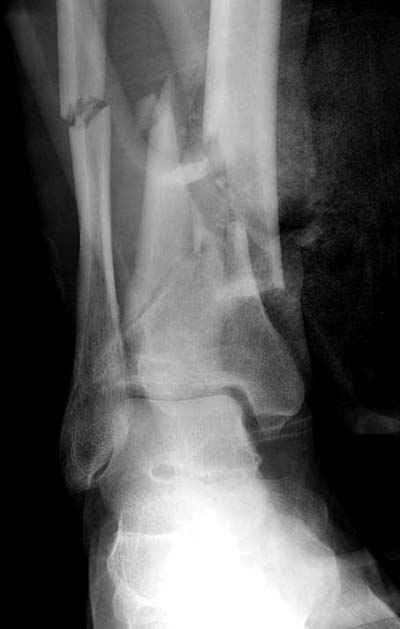

Представляю рентгенограмму перелома обеих костей голени, где определяется разрыв дистального межберцового синдесмоза.

Механизм травмы - подвернул ногу. На боковом снимке видно, что латеральная лодыжка поломана на уровне голеностопного сустава. Во время травмы, кроме воздействия крутящего момента на кости голени, происходило еще и стремительное движение тела больного вниз вместе с проксимальным отломком малоберцовой кости (сила земного притяжения), вследствие чего разрывается межкостная мембрана, передняя межберцовая связка (lig.tibiofibulare anterius), рудиментарная поперечная связка. На боковом снимке конец проксимального отломка ( в данном случае место прикрепления передней межберцовой связки) находится на уровне середины таранной кости. Соответсвенно, последняя разорвана. Смещение отломков костей голени по длине - около 2 см.

Соответственно, из составляющих ДМС осталась целой

лишь задняя межберцовая связка. Хирургу, который будет оперировать пациента, рекомендовано наложить шов передней межберцовой связки, и ввести позиционный винт выше ДМС.